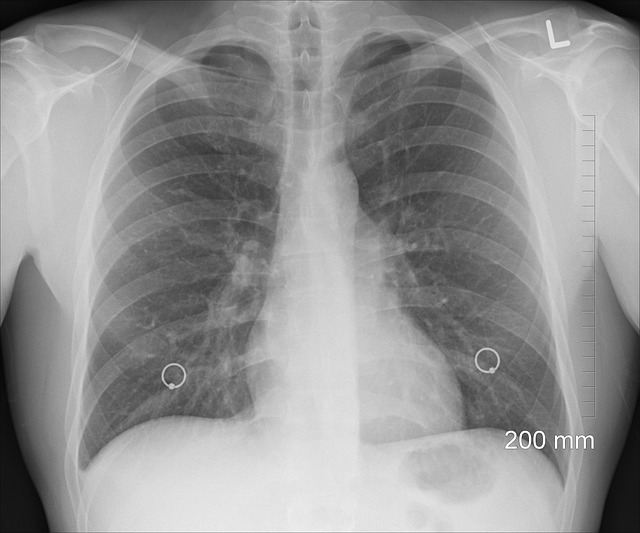

V České republice každý rok onemocní rakovinou plic přibližně 6 600 lidí a téměř 5 400 na ni zemře. Jejím prvním příznakem bývá úporný kašel, který navzdory léčbě neustupuje. Nemocní mívají potíže s dýcháním, hubnou a jsou unavení. Ohrožení jsou zejména současní nebo bývalí kuřáci ve věku

55–74 let. „Pokud lidé mají uvedené obtíže, měli by co nejdřív navštívit praktického lékaře. Ten je při podezření na nádor plic odešle na podrobnější vyšetření k pneumologovi. Správný typ léčby ale vybírají až lékaři v komplexních onkologických centrech,“ vysvětluje doc. Koblížek. Jaká konkrétní vyšetření by měli nemocní podstoupit, zjistí z Cesty pacienta s karcinomem plic. Dozví se také, kteří specialisté vyšetření provádí. „Jednoduše si tak zkontrolují, jestli se jejich cesta ubírá správným směrem. Absolvovat by měli například bronchoskopii nebo vyšetření zobrazovacími metodami, jako je CT hrudníku a horní části břicha,“ dodává předseda českých pneumologů. Průběh a délka diagnostiky je individuální a závisí na typu onemocnění a aktuálním stavu pacienta. Léčbu by ale podle docenta Koblížka měli pacienti zahájit ideálně nejpozději do 42 dní od první návštěvy lékaře. „Pokud to trvá déle, musí se v ordinacích aktivně ptát, kde je problém. I to pomůže celý systém zefektivnit,“ říká.